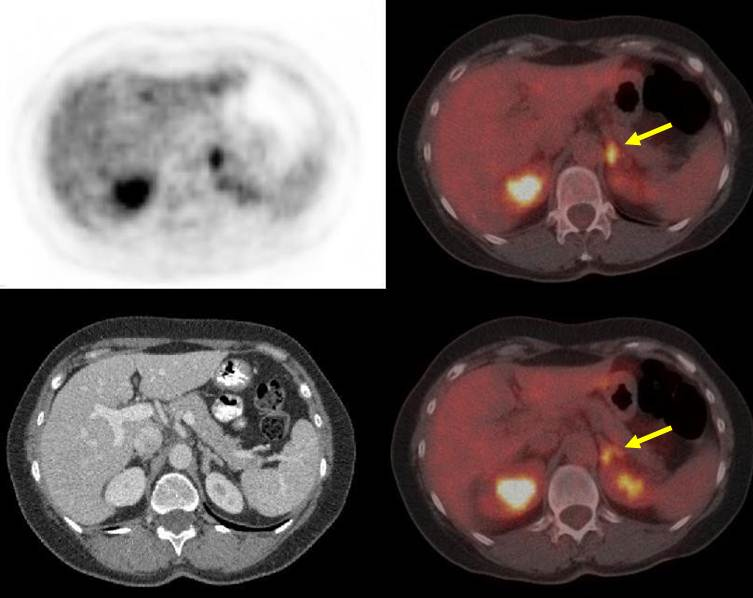

Además, se observó un área con incremento en la captación del radiotrazador en el hemisferio derecho del cerebelo. La masa mostraba un halo hipermetabólico acompañado de una zona central de posible necrosis, con un tamaño de 2,4x3,5x3 cm y SUVmax de 8,9 (SUV cerebelo: 6,6) siendo por tanto sugestiva de malignidad (fig. 2). Se evidenció también, un aumento patológico de captación en la glándula adrenal izquierda, con un tamaño de 1,5x2,5x3 cm y SUVmax de 7 (SUV del parénquima hepático: 3,4), por lo que se consideró también como sugestivo de malignidad (fig. 3).

La incidencia de metástasis adrenales de CRC es relativamente baja, entre 0,15 y 17,4%, con una media del 16% de acuerdo a diferentes publicaciones(12). Las metástasis adrenales se consideran resultado de una diseminación hematógena portal y sistémica y se asocian a enfermedad diseminada, con mal pronóstico(13-14). La PET/CT con 18F-FDG es una buena opción para localizar metástasis adrenales silentes, siendo en todos los casos requerida la confirmación histológica(15-16). En un estudio reciente, se evaluó la eficacia de la PET/CT en la detección de recurrencia o enfermedad metastásica en pacientes con historia de CRC y elevación de CEA, determinándose que el método posee un desempeño considerablemente mejor que la TC multicorte aislada(17). La resección quirúrgica parece mejorar la supervivencia en pacientes seleccionados, al tiempo que la quimio o radioterapia presenta pobres resultados para estas lesiones(12-13).